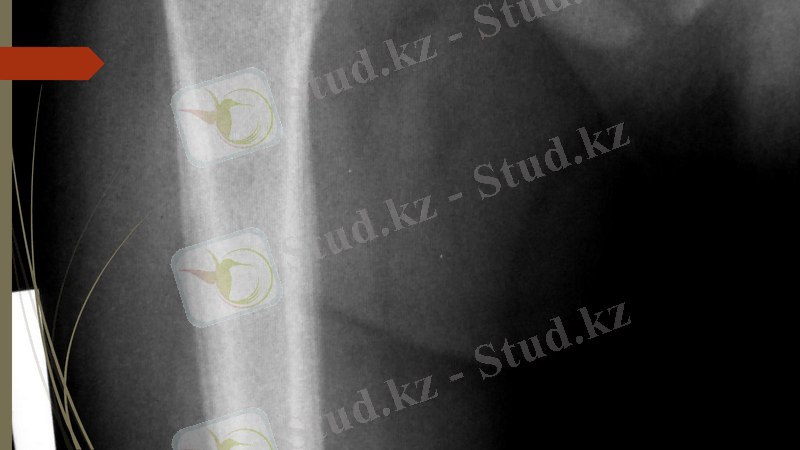

Рентген сәулесімен зерттеу әдісі - сүйек пен каңқаны зерттеп, диагноз қоюдағы ең жоғары сапалы эдіс болып табылады. Бүл әдістің тек сүйектін қүрылысын ғана емес, сондай-ақ сүйектену, сүйектің өсу динамикасын, тірек-қимыл системасының қимылдау кезеңіндегі ауруларын, сүйекті коршал түрған үлпалардың да ауруларын зерттеуде маңызы зор.

ІрІ малдардын сирағын рентгенограммаға түсіру әдістемесі

Тұяқтарды рентген суретке тік жэне қатпал проекцияда түсіреді. Жылқының, сиырдың алдыңгы тұяңтарын тік проекцияда түсіру. Кассетаны кигаш кондырғыга орналастырып, оньщ үстіне алдын-ала тазартылган ауру малдын тұягын кояды. ОСШ тұяк (венчик) арқылы кассетаның ортасына багыттайды